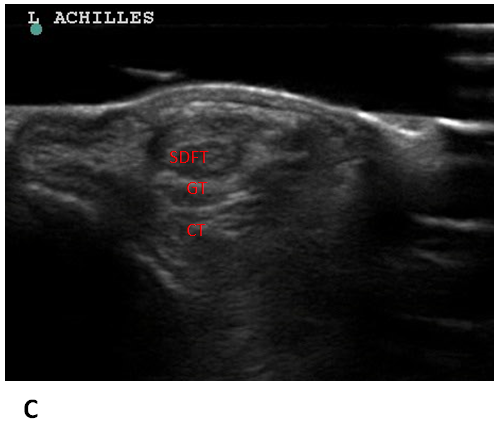

6 7 3 Partial Achilles Tendon Ruptures Ultrasound Cases